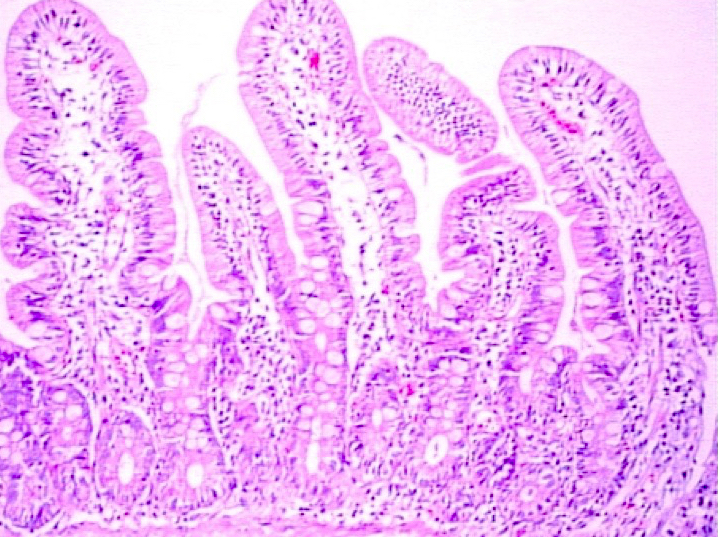

Microscopic (histologic) description

- Histological elementary lesions (Dig Liver Dis 2011;43:S385, Semin Diagn Pathol 2014;31:124):

- Increased intraepithelial T lymphocytes (IEL):

- 25 - 29 IEL/100 enterocytes is considered borderline

- > 30 IEL/100 enterocytes represents a pathological lymphocytosis

- Decreased enterocyte height, flattening of enterocytes, intracytoplasmic vacuolation and reduction or absence of brush border are suggestive but not specific

- Crypt hyperplasia:

- Extension of the regenerative epithelial crypts associated with changes in the presence of more than 1 mitosis per crypt

- Villous atrophy:

- Decrease in villous height, normal villous:crypt ratio (3:1) until total disappearance of villi

- This assessment requires proper orientation of the biopsies

- Increased intraepithelial T lymphocytes (IEL):

- Diagnostic categories are based on these elementary lesions:

- Modified Marsh-Oberhuber classification of histologic findings in celiac disease

- Simplified systems (Corazza & Villanaci or Ensari), which may be more reproducible (Arch Pathol Lab Med 2010;134:826, Pathol Res Pract 2016;212:1174)

- Different grades of duodenal mucosal lesions:

- Grade A / type 1: increased intraepithelial lymphocytes but no villous atrophy

- Grade B1 / type 2: villi still present but shortened

- Grade B2 / type 3: complete villous atrophy

Microscopic (histologic) images